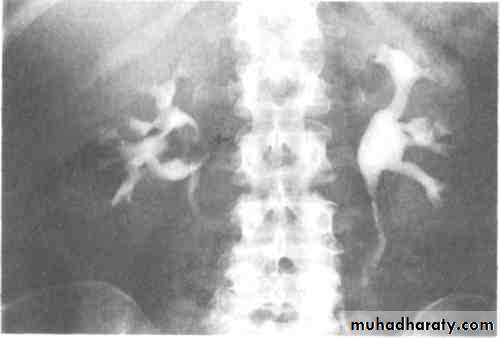

Poly cystic disease

Adult typePresent after the third decade of life , Familial.

Renal parenchyma is replaced by numerous cysts containing fluid , The cysts are of variable size ,

Clinically renal colic, loin mass , heamaturia and hypertension, Renal tissue interposed between the cysts after time dssimcted ended with renal failure

Almost bilateral.

IVU

Large kidney .

Lobulated out-line.

Distortion of pelvi- calyceal system depend on cyst size, number and position.

In advanced cases there is elongation and stretching of minor and major calyces ( spider leg).

In advanced cases IVU shows non-functioning kidney .